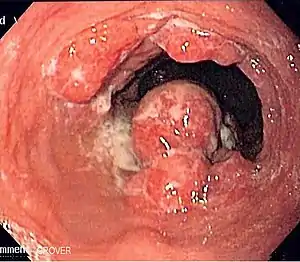

Endoscopic image of an esophageal adenocarcinoma

Although an occlusive tumor may be suspected on a barium swallow or barium meal, the diagnosis is best made with an examination using an endoscope. This involves the passing of a flexible tube with a light and camera down the esophagus and examining the wall, and is called an esophagogastroduodenoscopy. Biopsies taken of suspicious lesions are then examined histologically for signs of malignancy.